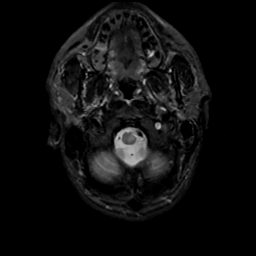

MR Study #16, June 23, 1991 -- Slice #3

[Home][Help][Clinical][Tour 1][Tour 2] Slice 3